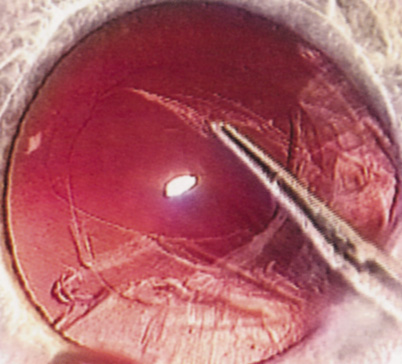

WHITE CATARACT

The introduction of innovative adjunctive devices was able to improve the management of challenging cases. The capsular tension ring introduced independently by Tsutomu Hara37 and Toshiyuki Nagamoto38 in Japan was identified as a major weapon in managing zonular weakness by Ulrich Legler and Bernd Witschel of Germany.39 The CTR came to the United States in 1993,40 after which modifications by Robert Cionni,41 Iqbalk Ahmed and Alan Crandall,42 and Burkhard Dick were developed. Iris reconstruction had been primarily limited to suture techniques developed by Malcolm McCannel43 and later Steven Siepser.44 The prosthetic irides were introduced by German surgeons, Ranier Sundmacher45 and Volker Rasch,46 and brought to the United States by Kenneth Rosenthal and then Robert Osher in 1996.47 Although many devices had been developed to mechanically open the small pupil, it was the stretch technique developed by Luther Fry that greatly simplified these difficult cases.48 Improving visibility by staining the anterior capsule of the white cataract was introduced by Masayuki Horiguchi from Japan (ICG)49 and Gerritt RJ Melles from The Netherlands (Trypan Blue).50